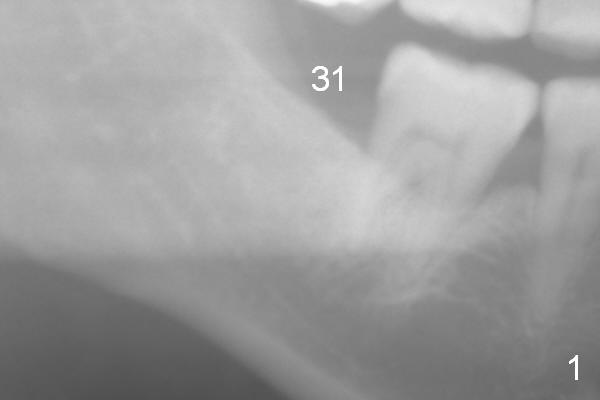

A 59-year-old lady has lost the tooth #31 for several years (Fig.1). In the last 7 years, the 1st molar has undergone mesial oblique bone loss (Fig.2 *). The apical half of the lamina dura has become denser (arrowhead). These 2 types of bone changes suggest occlusal trauma to the tooth, overloading because of missing #31. The upper 2nd molar appears to have been supraerupted more (Fig.2 black arrow). Before an immediate provisional is fabricated for the tooth #31, a short abutment is expected (possible 5841 or 6841).

Since panoramic X-ray does not show the nerve very well (Fig.1,2 yellow dashed line), a PA should be taken prior to surgery, as deep as possible. If the PA does not work, CT will be taken.

The buccolingual ridge should not be too wide. #15 is expected. For safety, an implant system with stoppers will be used for the area with poor visibility. Distance from the neighboring tooth is 5 mm (Fig.2 red lines). Set the 4 mm implant spacer with 2 mm pilot drill.